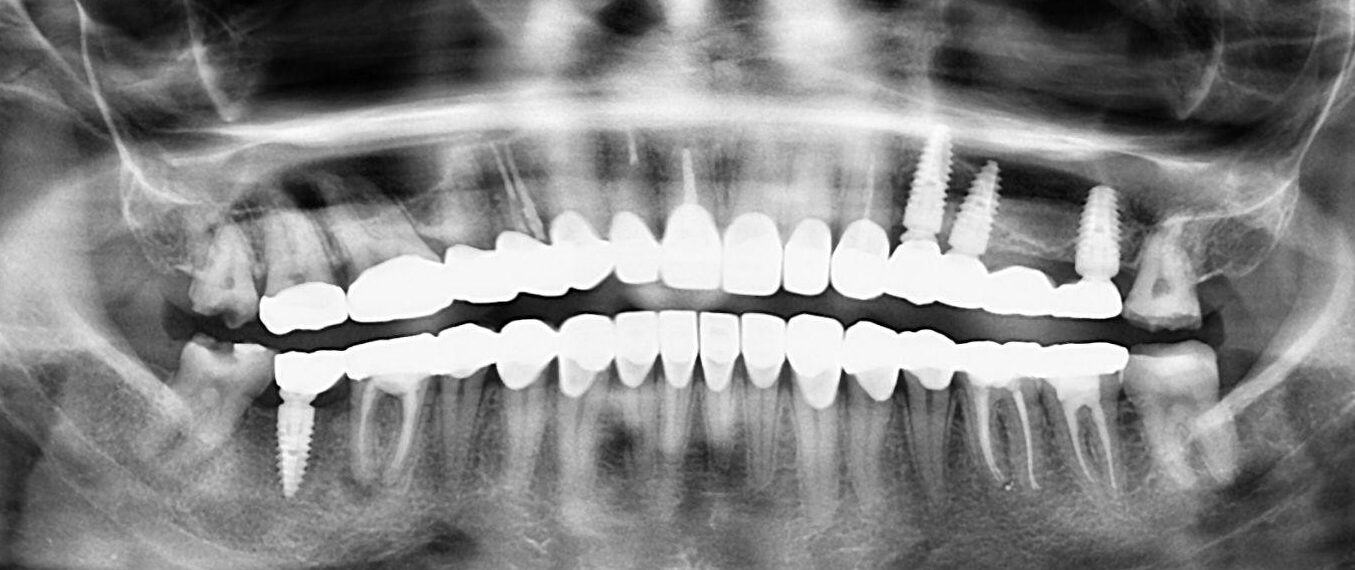

6. What option cannot be selected for this panoramic X ray?

7 / 23

7. What option cannot be selected for the upper jaw of this panoramic X ray?

8 / 23

8. What option cannot be selected for the lower jaw of this panoramic X ray?

9 / 23